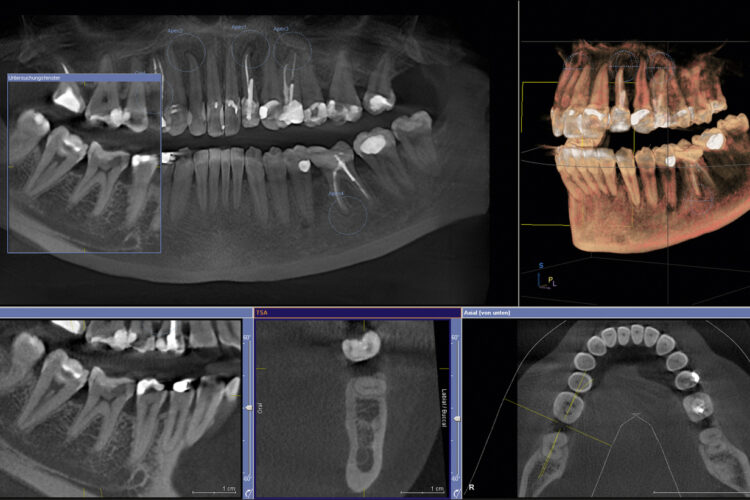

En la Clínica Dental Dr. Arias apostamos por la innovación tecnológica como base para ofrecer tratamientos más precisos, cómodos y seguros. Nuestra tecnología de última generación nos permite realizar diagnósticos inmediatos, planificar tratamientos personalizados y lograr resultados predecibles y estéticos.

Alta tecnología dental

Nuestra clínica está equipada con tecnología dental de vanguardia, lo que nos permite abordar desde tratamientos preventivos hasta procedimientos complejos con el máximo control y exactitud. La digitalización en odontología ha revolucionado la forma de tratar a los pacientes, y en la Clínica Dental Dr. Arias la aplicamos para ofrecer una atención más eficaz y personalizada.